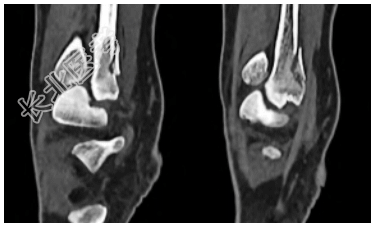

- [材料题] 患者,女,39岁,主诉“外伤致左踝部疼痛、活动受限1h”入院,就诊于日照市中医医院急诊外科。查体:左侧踝关节局部软组织肿胀压痛,后外侧压痛明显,踝关节活动受限,可触及足背动脉搏动,左侧下肢远端血运、感觉、活动未见明显异常。辅助检查:左侧胫腓骨(包括踝关节)X线片显示左侧腓骨远端骨折,骨折块在正位片被腓骨干遮挡(图1)。入院后完善踝关节CT检查,CT横断面显示左侧腓骨远端后侧骨折块,骨折块向胫骨侧移位,骨折线沿冠状面走形,左侧腓骨切迹为Ⅰ型,右侧腓骨切迹为C型(图2);CT矢状面显示左侧腓骨远端后侧骨折块,未累及腓骨干(图3)。CT三维重建显示左侧腓骨远端后侧类椭圆形骨折块,为明确有无下胫腓联合韧带断裂,完善MRI检查,MRI显示下胫腓前、后韧带均完整,下胫腓后韧带与骨折块相连(图4),牵拉骨折块向内侧移位,PDW序列显示下胫腓后韧带存在浅深两层且在部分层面存在融合。以上检查结果可明确诊断下胫腓后韧带腓骨端撕脱骨折。